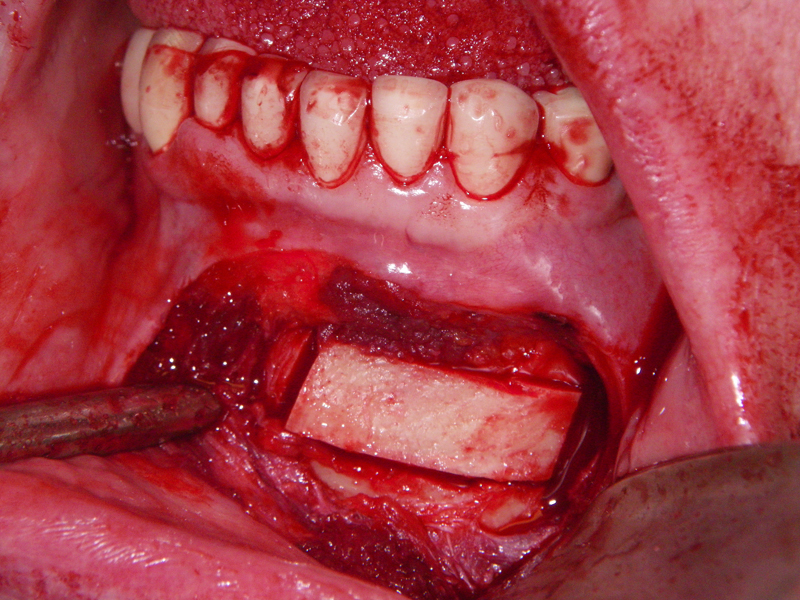

- Alveolar Ridge Augmentation

- Bone grafting – autogeneous, alogenic, xenogenic

- Blockgraft

- Incision

- Identify, don’t ‘skeletonize,’ mental nerves

- Midline, lateral score marks

- Osteotomy 5 mm below tooth apices & mental nerve

- Angulation of cut (Depends on planned movement)

- Downfracture (release ‘wings’)

- Fixation (plate, screws, wire)

- Layered closure (mentalis)